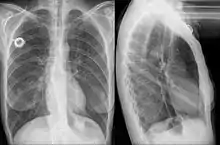

An esophageal stent is a stent (tube) placed in the esophagus to keep a blocked area open so the patient can swallow soft food and liquids. They are effective in the treatment of conditions causing intrinsic esophageal obstruction or external esophageal compression. For the palliative treatment of esophageal cancer most esophageal stents are self-expandable metallic stents. For benign esophageal disease such as refractory esophageal strictures, plastic stents are available. Common complications include chest pain, overgrowth of tissue around the stent and stent migration.

Esophageal stents are placed using endoscopy when after the tip of the endoscope is positioned above the area to be stented, then guidewire is passed through the obstruction into the stomach. The endoscope is withdrawn and using the guidewire with either fluoroscopic or endoscopic guidance the stent is passed down the guidewire to the affected area of the esophagus and deployed. Finally the guidewire is removed and the stent is left to fully expand over the next 2–3 days.